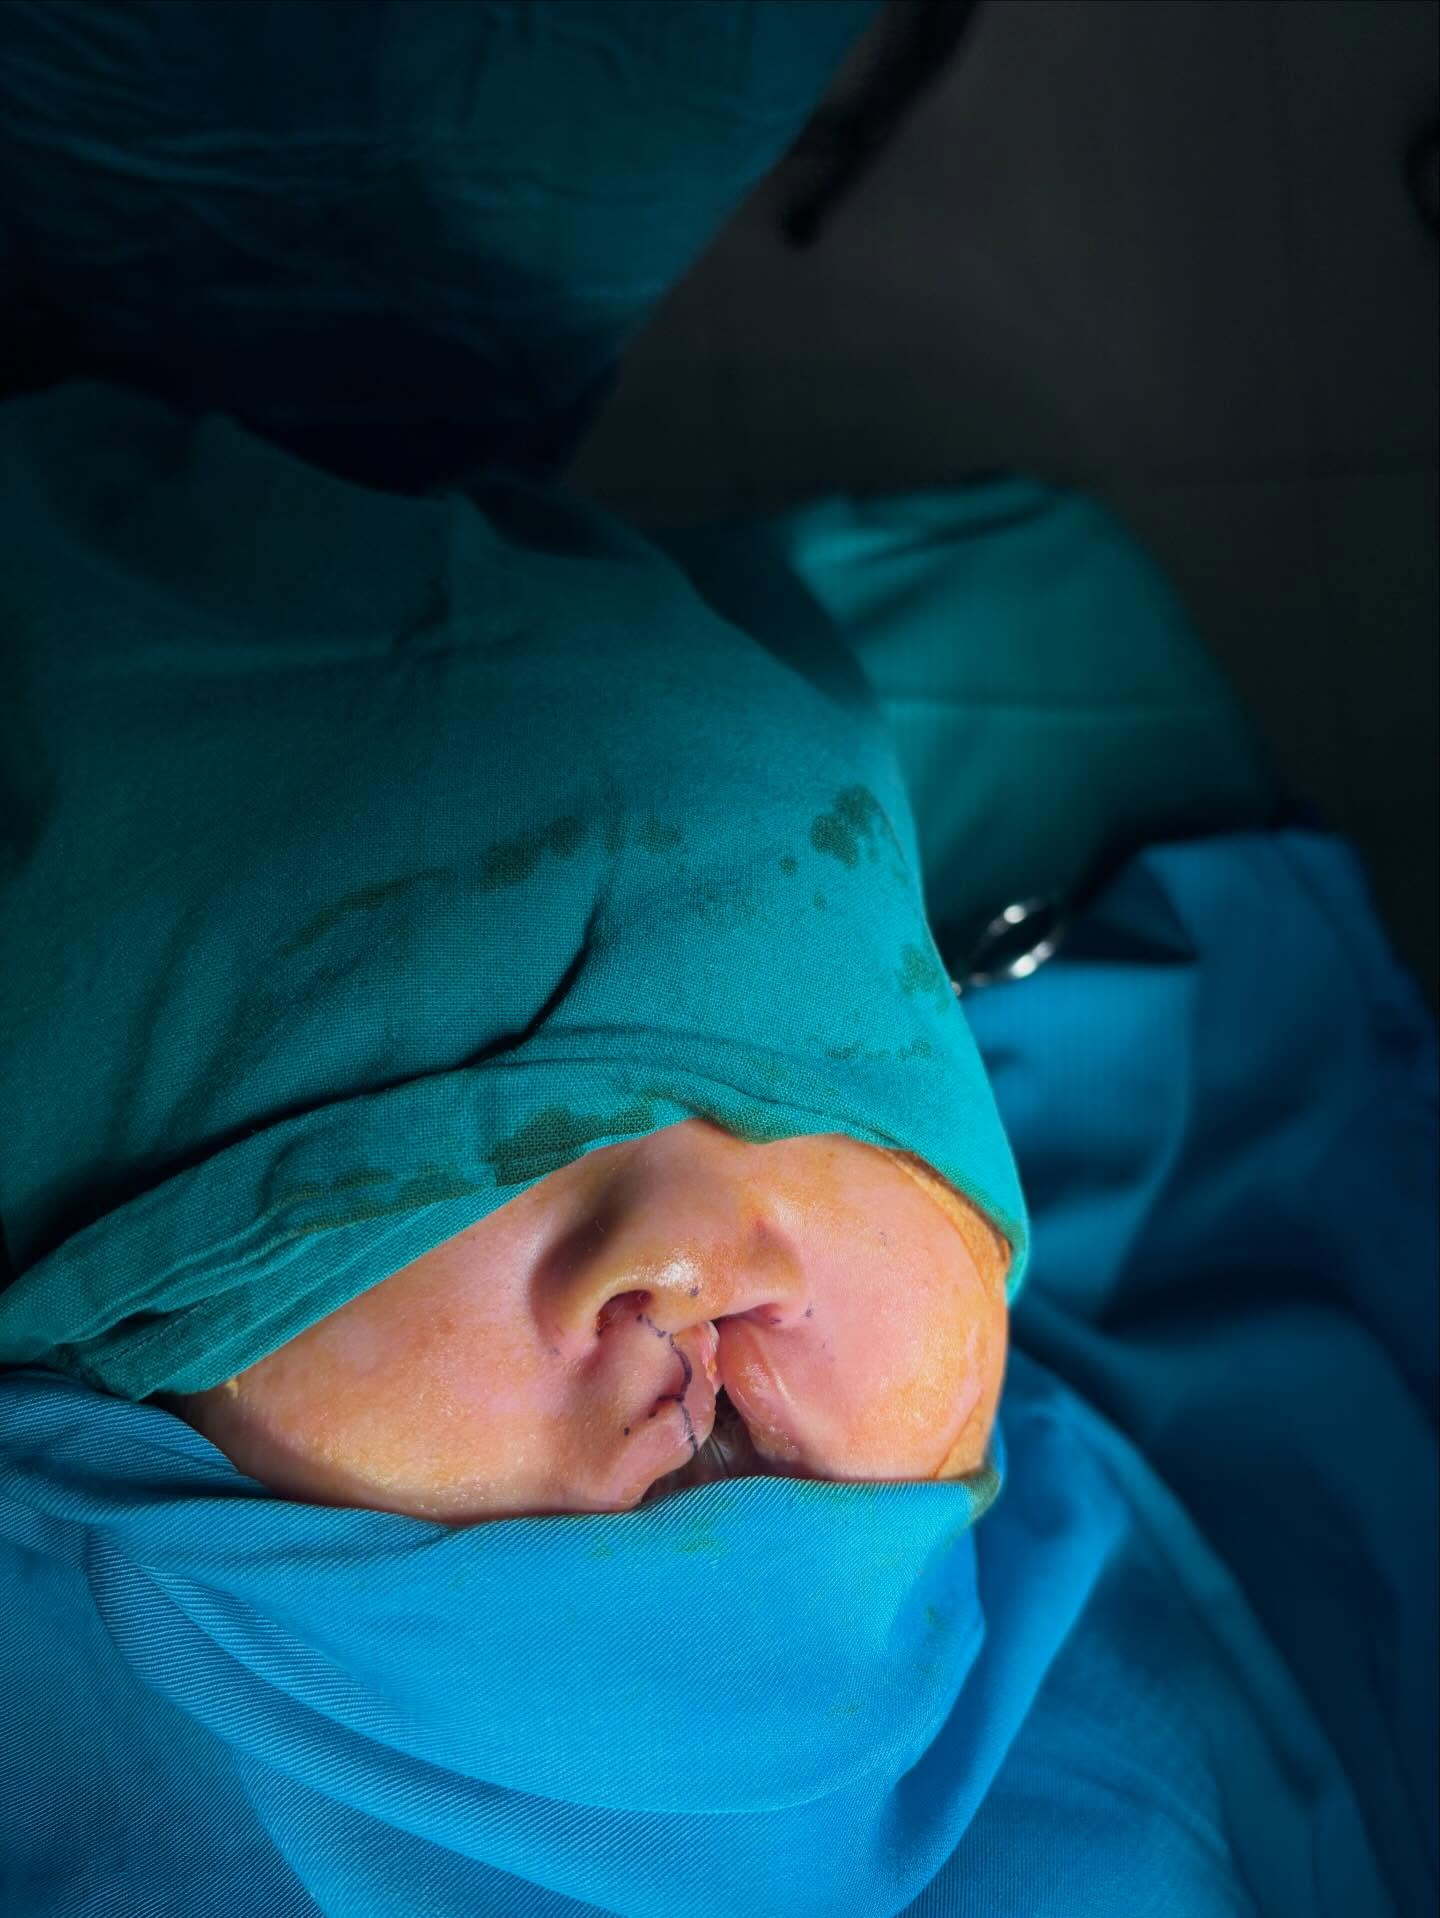

口蓋裂オペです

午後からも口蓋裂オペ

今日の患者さんも口蓋裂のオペです!術前診察して準備開始です。

今日の手術の患者さん

生後3か月の赤ちゃん

小さい手,小さい足、本当に可愛い赤ちゃん

綺麗に唇が閉じて終わったらもっとお母さんが笑顔になってくれたら嬉しい

無事に手術も終わってお母さんもとっても喜んでくれました

唇裂の手術は見た目もすごく変わるので喜びが大きいですね

綺麗になって良かったです